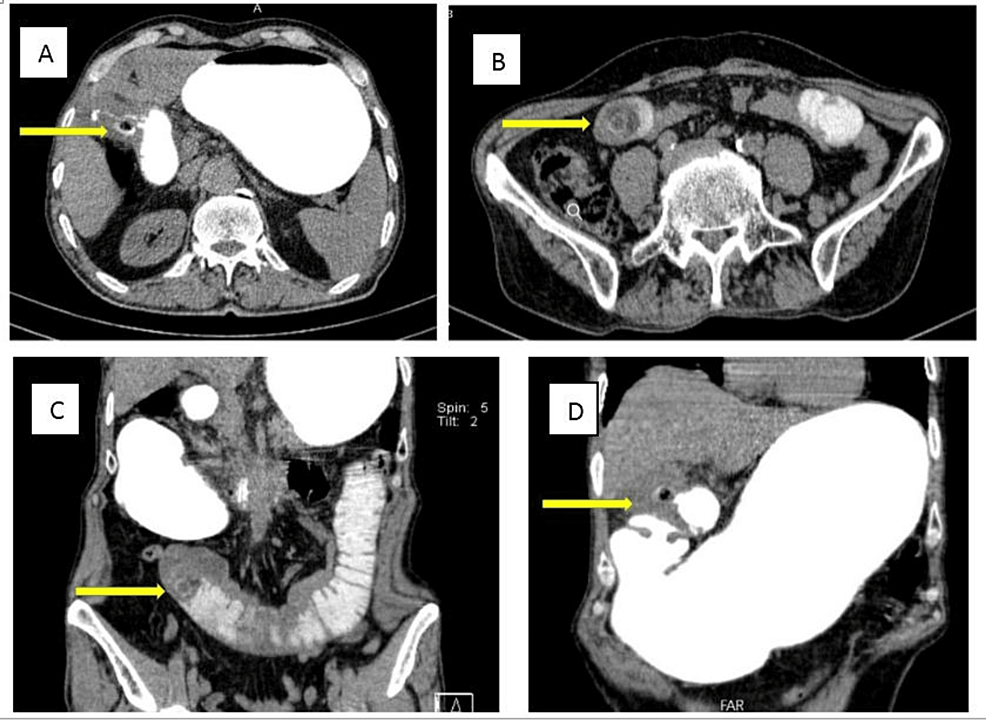

Upright abdominal X-ray showed mildly dilated small bowel loops (Figure 1). An abdominopelvic CT scan with oral contrast was performed. Findings were compatible with gallstone ileus: dilated duodenal and jejunal loops, fistulous tract between gallbladder wall and duodenal bulb, oral contrast leakage to gallbladder lumen, obstructing layering gall bladder stone in the jejunum, and at least two other stones in the gall bladder (Figure 2).

Due to poor patient compliance and surgery refusal, as well as partial obstructive symptoms, conservative management was chosen at first, inevitably. But his symptoms and signs worsened during the first three days of admission, including bilious vomiting, obstipation, increasing abdominal pain, distention, and leukocytosis in favor of complete obstruction. Finally, the decision was made to perform an urgent laparotomy after getting informed consent.

The intraoperative examination showed dilated duodenal and jeujonal non-ischemic loops, impacted jejunal stone at the transitional point, and adhesions over the gallbladder and duodenal wall. An enterotomy was done using a longitudinal incision. An oval-shaped stone measuring 28 x 25 mm and biliary material were extracted, and then the double layer closure of enterotomy was performed. The remainder of the gastrointestinal tract was assessed carefully to find other ectopic stones, but none were found. The area of the cholecystoduodenal fistula was not manipulated due to the patient’s condition and potential risk of injury due to extensive adhesions.

On the fifth postoperative day, after beginning an oral diet, mild colicky abdominal pain and bilious vomiting were revealed. A second abdominopelvic CT scan with oral contrast was performed, which demonstrated another duodenal ectopic non-obstructing gallbladder stone measuring 17 x 15 mm with a typical Mercedes-Benz sign in favor of recently migrated gall stone (Figure 3). Since the patient had no obstructive symptoms, conservative treatment and follow-up were opted for.

Inflammatory changes, pressure erosion, and ischemia of the gallbladder wall could lead to biliary-enteric fistula in patients with a long-standing history of gallstone disease. Cholecystoduodenal fistula is the most common manifestation (32.5-.96.5%) [3] as shown in our case, which was well demonstrated in the CT scan.

Radiological imaging is the cornerstone for the early diagnosis of gallstone ileus. The classic Rigler’s triad illustrates the radiographic features of gallstone ileus: small bowel obstruction, pneumobilia, and an ectopic gallstone that migrates in serial films through the GI tract; the presence of two of them is enough for gallstone ileus diagnosis. Only 10% of gallstones are radiopaque, and this along with the presence of fecal material renders plain abdominal radiography incapable of detecting gallstones and reduces the chance of an early diagnosis [13]. Ultrasound helps to make a correct diagnosis by detecting cholelithiasis, fistulous tract, and pneumobilia. Interestingly, no aerobilia detected by ultrasound may have a role in delayed diagnosis [14,15]. Enhanced CT scan is the most effective diagnostic modality in terms of sensitivity and specificity (93% and 100% respectively), and it is associated with several benefits, such as determining the viability of the involved segment of the bowel preoperatively and providing information for a decision-making strategy and therapeutic approach [16].

Lassandro et al. found that the Rigler’s triad is observed in 14.8% of cases via plain abdominal radiography, 11.11% of cases on ultrasound examination, and 77.78% on abdominal CT scan [14]. In our patient, the Rigler’s triad was present on the CT scan, but it was not clearly visible on the abdominal X-ray. A correct preoperative diagnosis has been reported only in 50% of cases. Sometimes, gallstone ileus is diagnosed during surgery in patients with an unknown cause of small bowel obstruction [17].

As mentioned before, our patient underwent enterolithotomy alone, and the main reasons for preferring this approach were severe inflammatory changes and many adhesions around the gallbladder, which increased the risk of iatrogenic injuries. Also, the patient’s advanced age, presence of comorbidities, and poor compliance played a role in this decision. In the case of the second ectopic stone, which was detected in the follow-up CT scan, we preferred conservative treatment over re-enterolithotomy due to the stone size and absence of clear obstruction signs, and it passed through the GI tract, fortunately. CT scan had a significant role in our decision-making, as it enabled us to estimate the size and location of the stone and choose the non-surgical option for treatment.